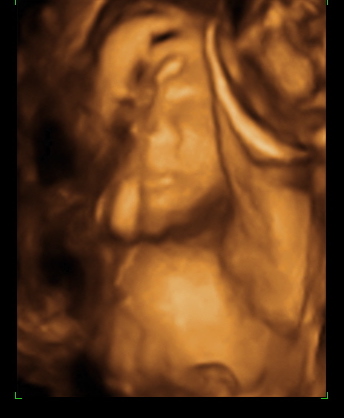

Both babies have been very active for quite some time now and it seems like at almost every OB visit someone doesn't want to cooperate, this time it happened to be our little princess with her arm across her face ... the ultrasound tech said she was being a little dramatic yesterday !!

Stella